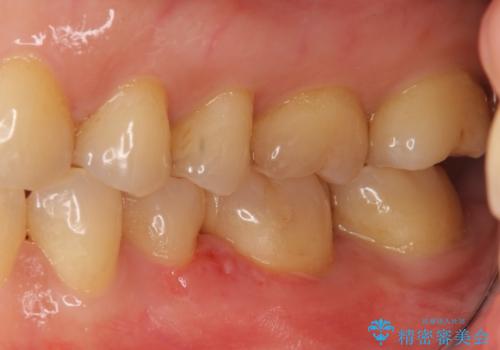

目立つ銀歯を全て白く セラミックで虫歯治療

- 銀の詰め物が気になるとのことで来院。

2本隣り合っているつめものを、同時にやりかえをしました。

- 14万円(左下5・左下6 emaxプレスインレー 7万円 x 2)費用は治療当時の料金となります

向かい合う銀歯を同時にやり変えることで、コンタクト(歯と歯の間の形)を理想的に仕上げることができ、ものも挟まりにくいように仕上げることができます。